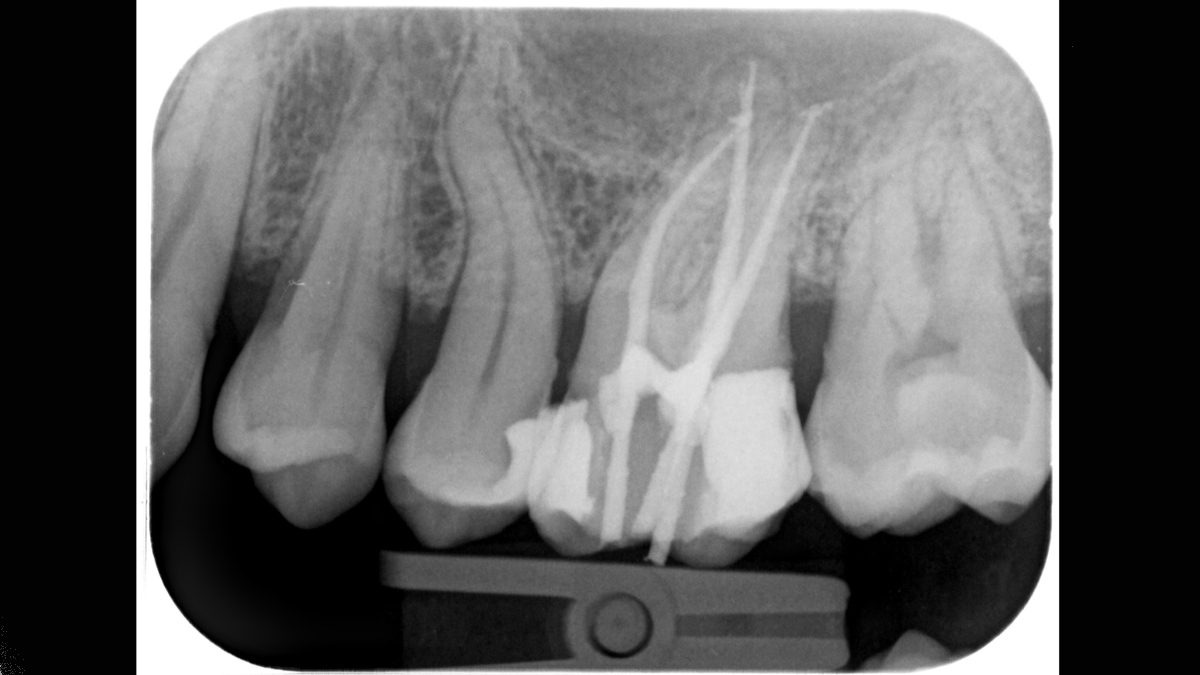

Xios Scan provides a gentle, easy introduction into the world of digital X-ray imaging. If you want to switch from film to digital without having to give up your tried-and-true working methods, imaging plate technology offers you a myriad of possibilities. You can experience many of the advantages of digital imaging without a darkroom and chemicals while your team continues its regular workflow.

The Xios Scan integrates seamlessly with the Dentsply Sirona X-ray units and software to deliver better, safer and faster intraoral diagnostics.